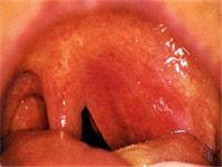

老先生三年前你得扁桃體癌,今天食管也有問題。這個病人患有扁桃體癌,現在又患上了食管腫瘤。當天她被確診為扁桃體癌晚期和口腔癌晚期。但是一看您這個病史有扁桃體腫瘤,然后食管也有腫瘤,無一例外。...